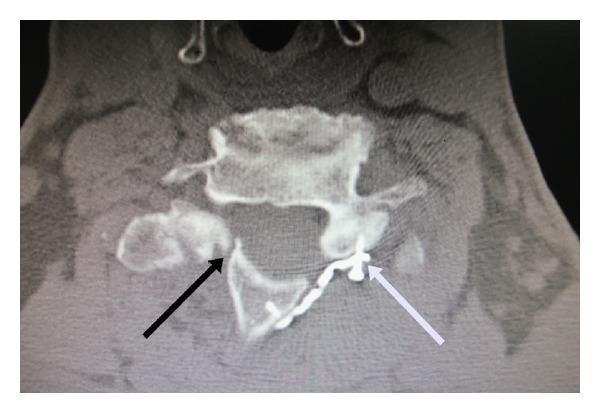

Background. One of the important complications of open-door laminoplasty is a premature laminoplasty closure. In order to prevent premature laminoplasty closure many techniques have been described and a titanium miniplate is one of the instruments to maintain cervical canal expansion. This study was performed to evaluate the effectiveness of titanium miniplates on the union rate for open-door laminoplasty. Materials and Methods. We performed open-door laminoplasty in 68 levels of fourteen patients using maxillofacial titanium miniplates. Axial computed tomography scans were obtained at 6 months postoperatively to evaluate the union rates of the hinge side. The Japanese Orthopedic Association (JOA) score was used to compare the clinical outcomes before and after surgery. Results. Computed tomography scan data was available on 68 levels in 14 patients. There were no premature closures of the hinge or miniplate dislodgements. The union rate on the hinge side was 70.5% (48/68). The mean JOA score increased significantly from 7.0 before surgery to 10.2, 12.2, and 13.0 after surgery at 1, 3, and 6 months, respectively. Conclusion. Open-door laminoplasty using maxillofacial titanium miniplates can provide union rates comparable to other techniques. It can maintain canal expansion without failures, dislodgements, and premature closures.

背景。开门式椎板成形术的重要并发症之一是椎板成形术过早闭合。为了防止椎板成形术过早闭合,人们描述了许多技术,钛微型钢板是维持颈椎管扩张的器械之一。本研究旨在评估钛微型钢板对开门式椎板成形术融合率的有效性。材料与方法。我们使用颌面钛微型钢板对14例患者的68个节段进行了开门式椎板成形术。术后6个月进行轴向计算机断层扫描,以评估铰链侧的融合率。采用日本骨科学会(JOA)评分比较手术前后的临床结果。结果。14例患者的68个节段均获得了计算机断层扫描数据。铰链处无过早闭合或微型钢板移位。铰链侧的融合率为70.5%(48/68)。JOA评分术前平均为7.0,术后1、3和6个月分别显著提高到10.2、12.2和13.0。结论。使用颌面钛微型钢板的开门式椎板成形术可提供与其他技术相当的融合率。它可以维持椎管扩张,而不会出现失败、移位和过早闭合。